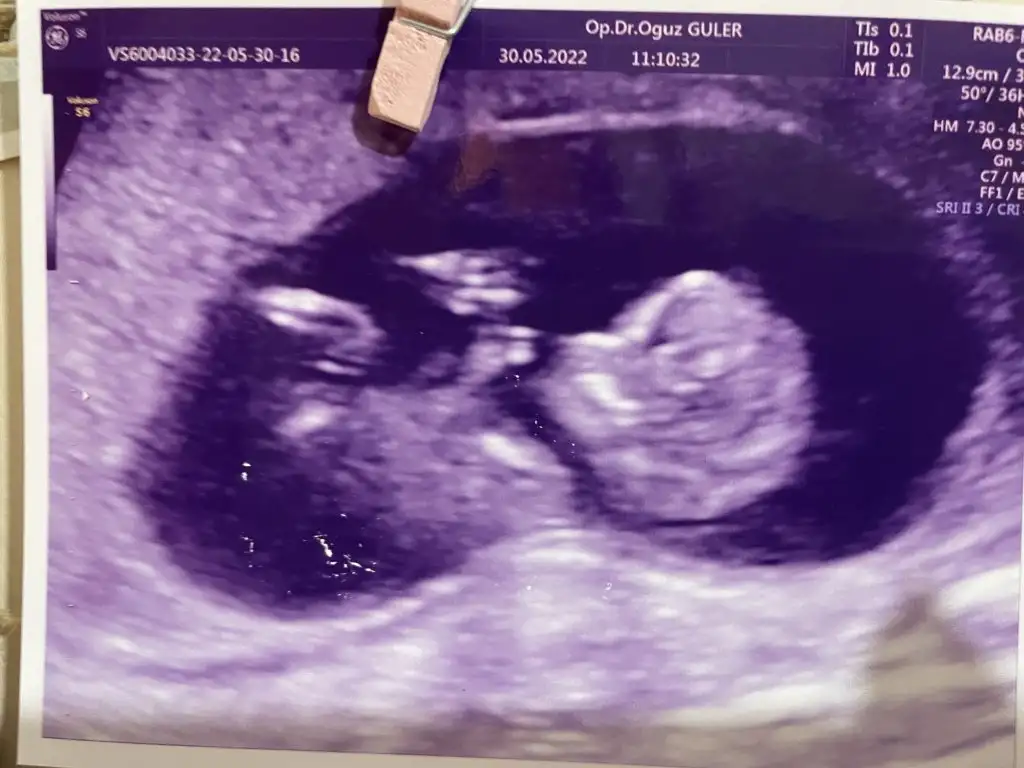

Bende merak ettim bana da bir bakar mısınız? Bugün gittim doktora henüz öğrenemedik 😊 12+5 karından bakıldı

89BACFD2-6748-4B88-946E-5142EC24D3AE.webp

Bizim için bir defa kız bir defada erkek yorumunda bulunmuştunuz, haftaya cinsiyet öğreneceğiz bizim görüntümüzü tekrar inceler misiniz cinsiyeti öğrenince mutlaka dönüş yapacağım :) Ultrason karından görüntü